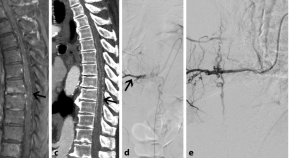

Spinale Gefäßmissbildungen